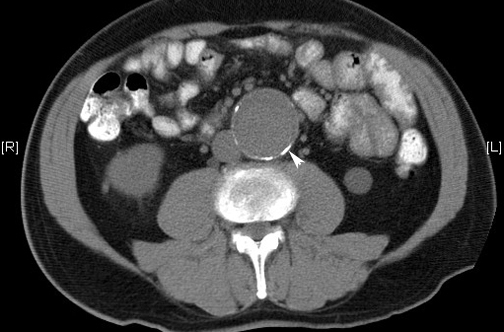

Aten Primaria, enero de 2019 La ecografía en atención primaria realizada por médicos de familia tras una formación básica para detección de de aneurisma de aorta abdominal (AAA) muestra muy alta validez diagnóstica. Habría que valorar con estudios más amplios de efectividad la pertinencia de implantar un sistema de detección precoz de AAA en población de riesgo.